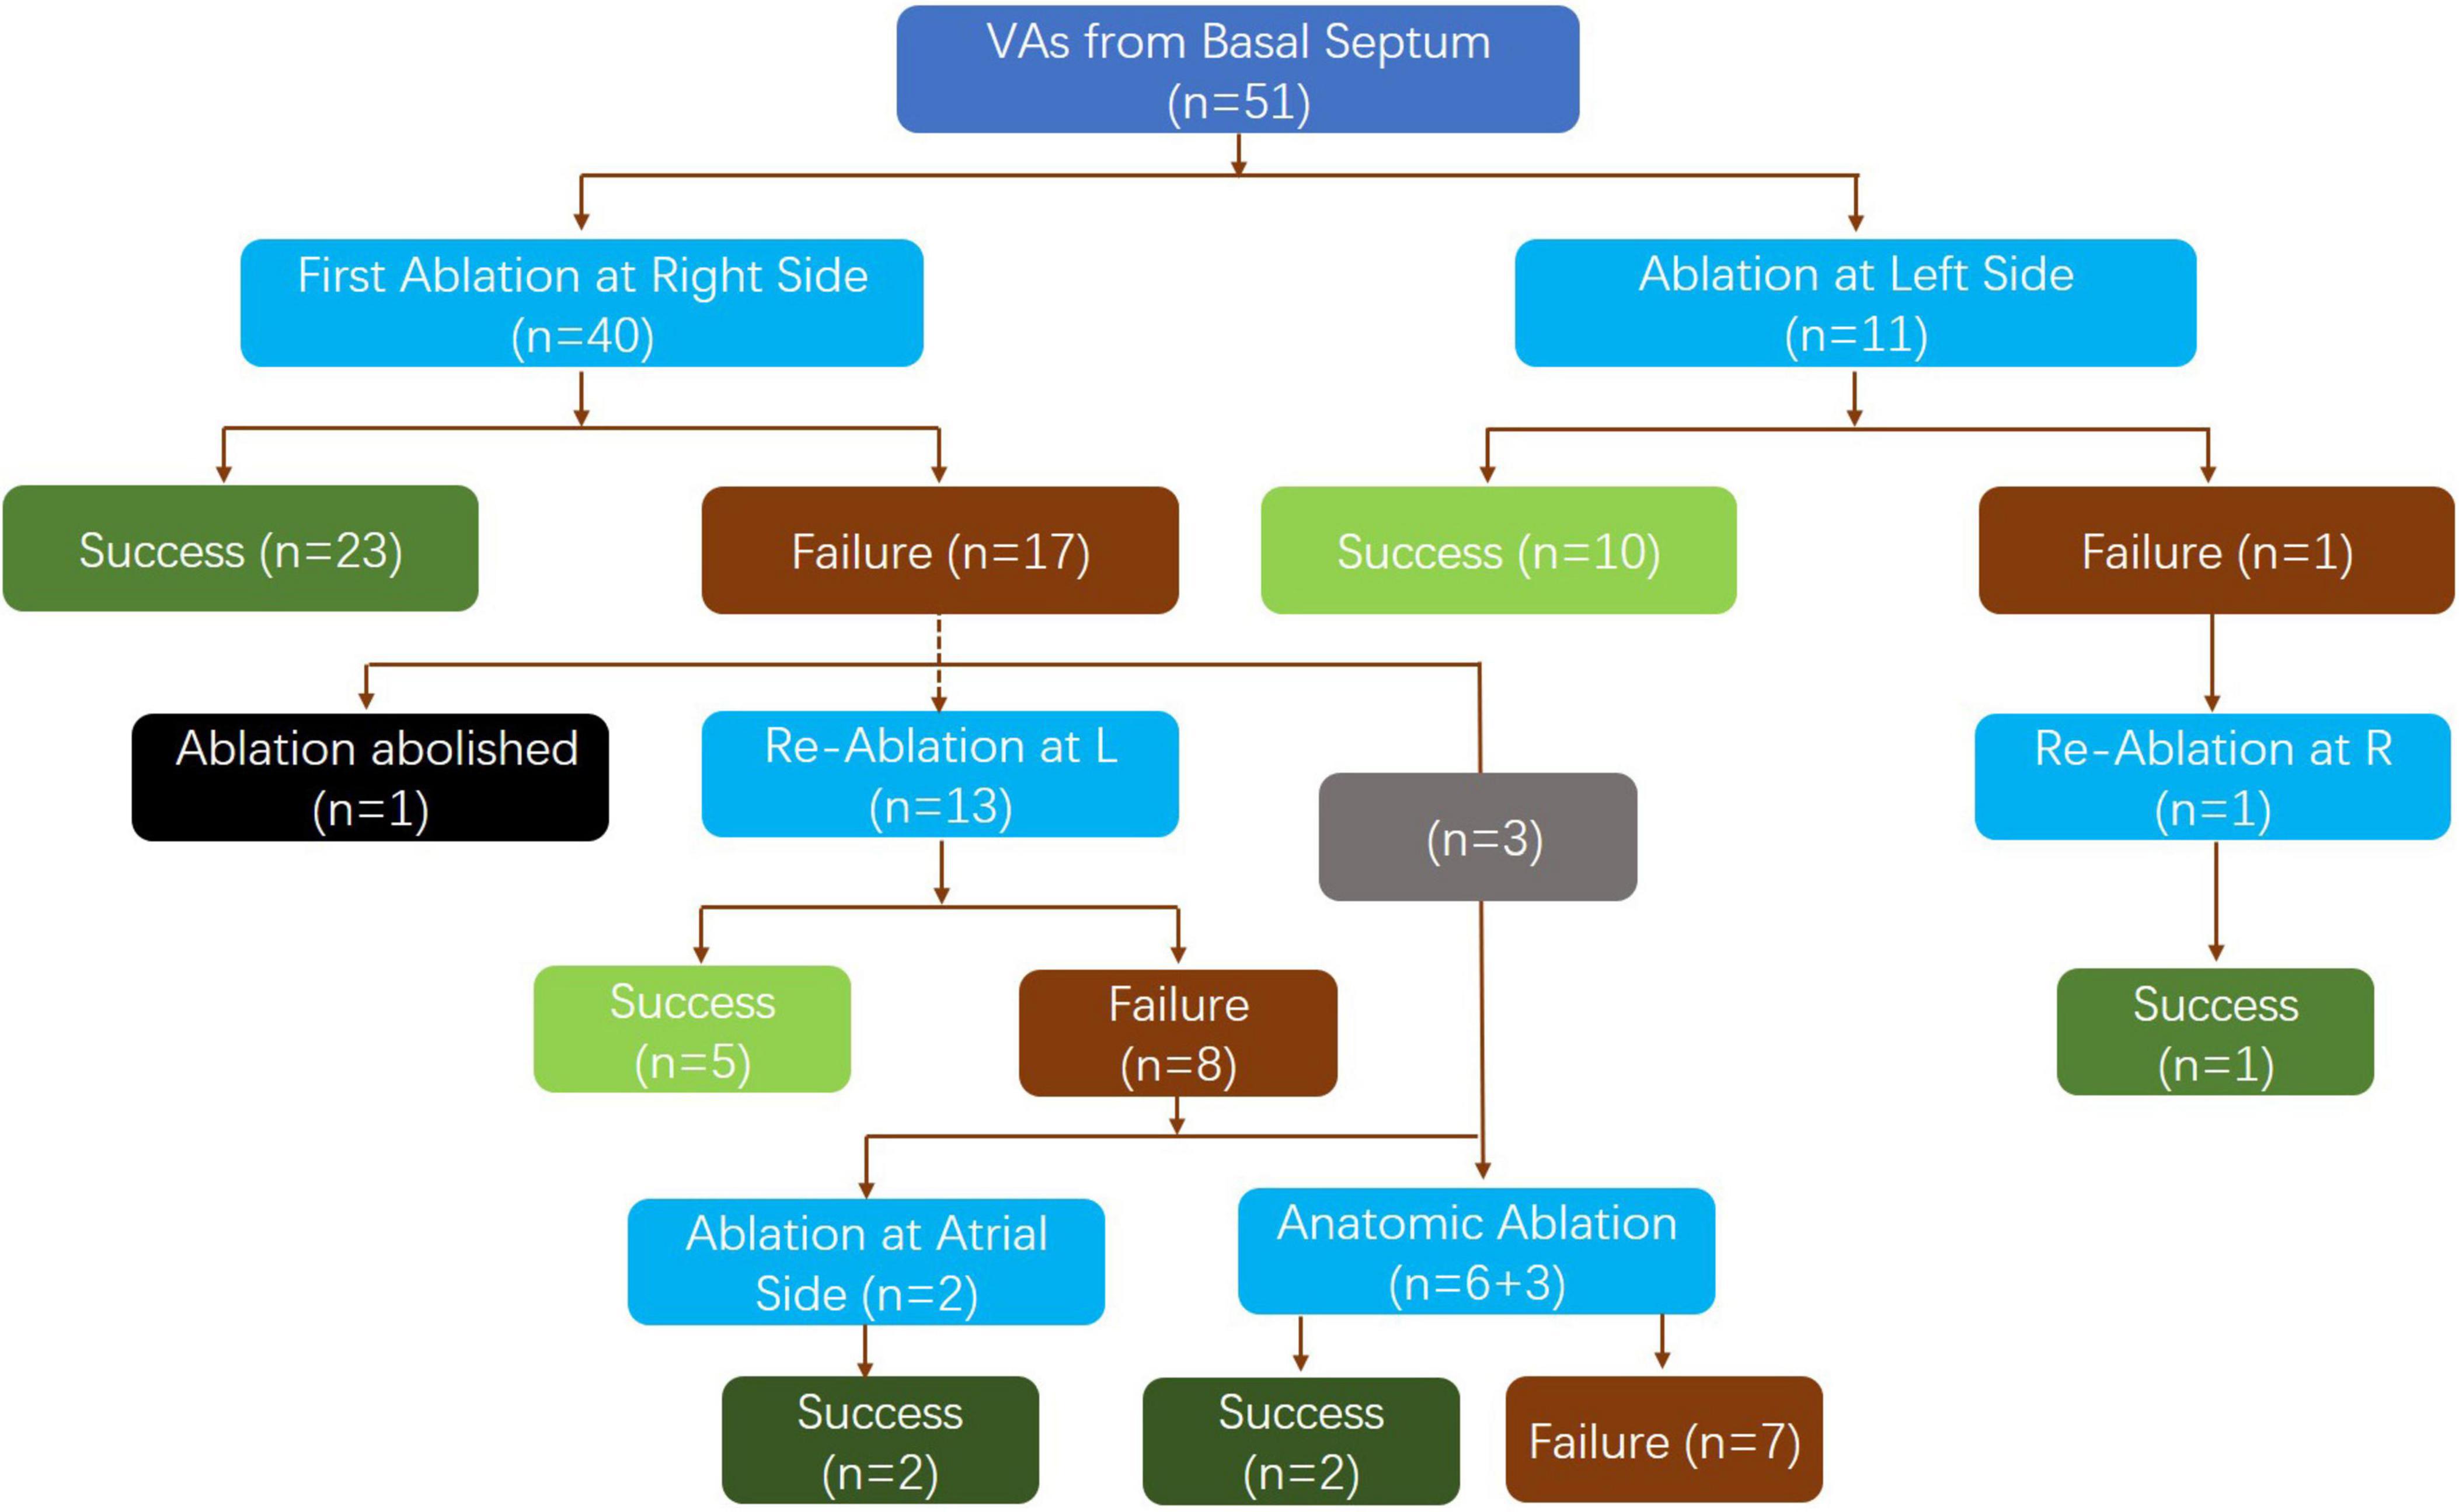

In the first attempt of ablation, an under-valve approach was used to target the earliest activation at the basal septum in 40 patients on the right side (Figure 1). Successful ablation of PVCs was observed in 23 patients. Remapping at the bilateral side of the basal septum was performed in the 17 patients whose initial ablation failed. At this step, the procedure was canceled in one patient due to pericardial effusion. In the remaining 16 patients, the shift of the earliest activation to the contralateral side was observed in 13 patients, while no obvious existing shift was detected in another 3 patients. Consequently, ablation at the left side was performed in 13 patients, with the VAs abolished in 5 patients. Among the 8 patients, VAs was abolished by atrial side ablation at the area of the slow pathway in two cases. Finally, anatomical ablation at both sides of the septum was performed in 9 patients, with success achieved in two patients and failure in the other 7 patients due to the transient suppression effect of VAs by ablation (4 patients) and signs of atrial ventricular conduction impairment (3 patient).

Left-side ablation was initially performed in 11 patients (retrograde aortic approach in 8 patients and transseptal approach in 3 patients due to instability of the mapping catheter in the retrograde aortic approach), and it successfully eliminated the VAs in 11 patients. After remapping on both sides, one patient who failed ablation on the left side had the VA successfully ablated by right-side ablation under the valve.

The detailed ablation results are provided as a flowchart in Figure 1. The anatomical distribution of the VAs is delineated in Figure 2. Then, according to the site of successful ablation, patients were categorized into Group 1 (right side), Group 2 (left sight) and Group 3 (intramural foci).